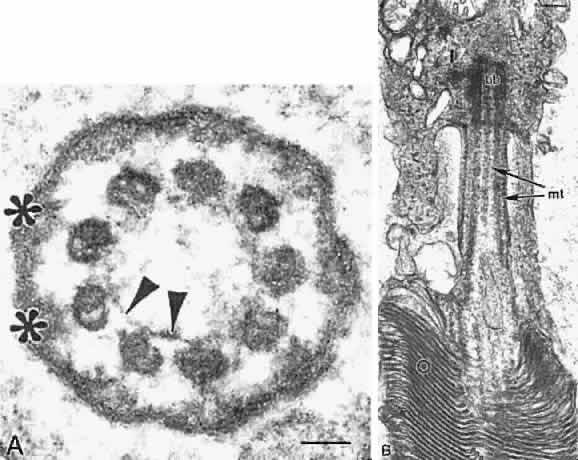

The photoreceptor outer and inner segmentsare joined by a thin stalk, the connecting cilium(Fig. 11). This cilium originates in a basal body (centriole) in the inner segment and as viewed in cross section by electron microscopy contains a ring of nine microtubule doublets typical of a sensory cilium. A central pair of microtubules, characteristic of motile cilia, is absent in the photoreceptor connecting cilium. The cilium is the only connection between the outer and inner segments and is thought to function as a conduit for transport of newly synthesized proteins such as visual pigments from the inner to the outer segment.

Fig. 11. Electron microscopy of connecting cilia of human photoreceptors. A. Cross section of cilium. Note nine doublets of microtubules forming a ring characteristic of sensory cilia. The microtubules are interconnected by nexin links (arrowheads) and joined to the surface membrane by Y-shaped linkers (*). Bar = 0.04 μm. B. Longitudinal section of cilium. Note microtubules (mt), stacks of membrane discs in the outer segment (O), and basal body (bb) in the inner segment (I). Bar = 0.15 μm.